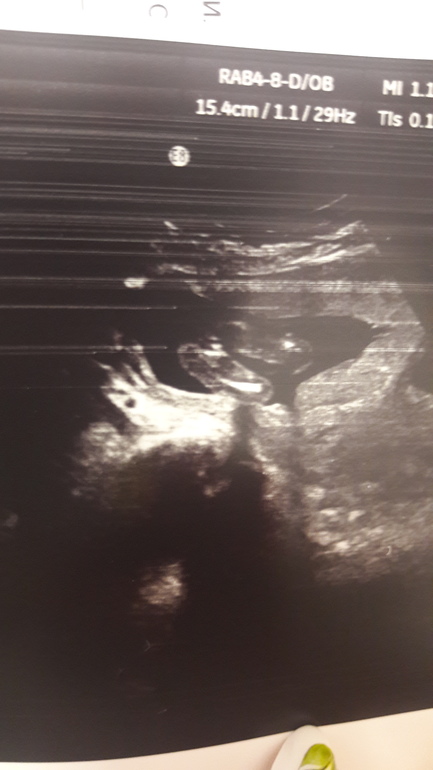

УЗИ, КТГ, доплерТем,кому еще я не надоела)))))А вот на этом фото моя фантазия упорно мне рисует мальчика.Неужели меня моя интуиция подводит.....Мой маленький инопланетянин))))) в 16-17 н

Я бы верила больше фото где между ног, так как на фото в посте малыш смотрит на нас и там ничего не видно что между ног у него. На вашем сроке грамотный врач не ошибается. Я своих на этом же сроке рассекретила)))